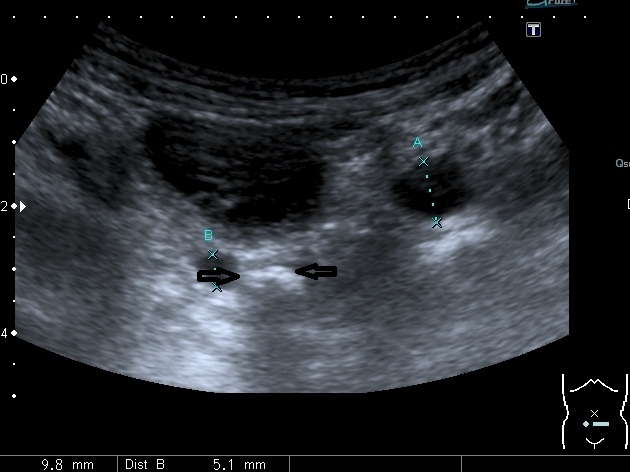

Мочеточники в нижней трети

Если честно, и я изначально не совсем понял, где находится конкремент (а это конечно же конкремент), локализованный на урограммах. При первичном исследовании на УЗИ его я не видел (либо он спрятался за тенью конкремента мочевого пузыря, либо я обрадовался редкой находке конкремента такого размера в мочевом пузыре - 2.5 см, и не посмотрел что ниже). Тем не менее при ретроспективном анализе архивированных сонограмм, как мне кажется, он попал в один из сканов, м.б. не совсем чётко.

I20111114160229796.jpg

И всё -же, где конкремент :?:

Возможно, в дивертикуле либо в нижней трети мочеточника..

Верификация:

Выдержка из протокола операции- "...вскрыт мочевой пузырь, обнаружен камень 4 х 3х 2.5 см, плотный, удалён. При дальнейшей ревизии мочевого пузыря обнаружен вколоченный камень в шейке мочевого пузыря и в уретре, удалён камень 2 х 1.5 х 1.5 см. При осмотре устья левого мочеточника - последний зияет, мочеточник расширен до 1 см, учитывая расширение мочеточника, проведена антирефлюксная пластика по Грегуару..."